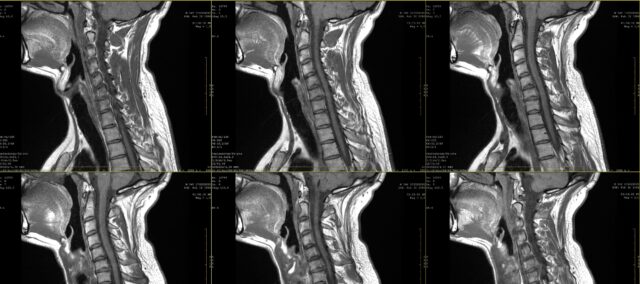

للتحقق من الاتفاق بين رسومات الألم الجذري ونتائج التصوير بالرنين المغناطيسي، شملت هذه الدراسة مشاركين لديهم تاريخ مرضي من الألم المستمر لمدة شهرين، وتم تشخيصهم باعتلال الجذور العنقية على التصوير بالرنين المغناطيسي. تم إجراء هذا التشخيص من قبل جراح أعصاب بناءً على المعلومات السريرية ونتائج التصوير بالرنين المغناطيسي كما تم تقييمها من قبل أخصائي الأشعة.

تم عمل رسومات الألم على مخططات الجسم، سواء من المنظر الأمامي أو الخلفي. تم عرض هذه المخططات بعد ذلك على 4 أطباء (جراحان وأخصائيان في العلاج الطبيعي) الذين لم يكونوا على علم بجذر العصب المصاب كما هو محدد في فحص التصوير بالرنين المغناطيسي. لم يتلقوا سوى معلومات تفيد بأن جميع المرضى الذين عُرضت عليهم رسومات الألم، تم تشخيصهم باعتلال الجذور العنقية في مستوى واحد فقط بين C4 و C7. واستناداً إلى رسم الألم للمريض، كان عليهم تحديد مستوى العمود الفقري المصاب. تم تقييم الاتفاق بين مستوى العمود الفقري الذي تم التحقق منه بالتصوير بالرنين المغناطيسي وتقدير الطبيب القائم على رسم الألم باستخدام اختبار كابا. وعلاوة على ذلك، تم فحص الاتفاق بين المُقيِّمين باستخدام إحصائية كابا أيضًا. تم تفسير قيم Kappa على النحو التالي: